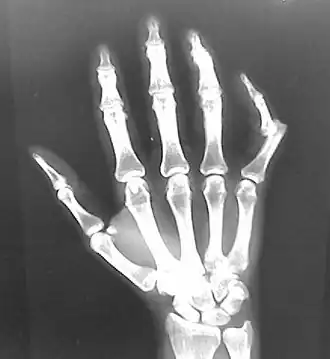

A joint dislocation, also called luxation, occurs when there is an abnormal separation in the joint, where two or more bones meet.[1] A partial dislocation is referred to as a subluxation. Dislocations are commonly caused by sudden trauma to the joint like during a car accident or fall. A joint dislocation can damage the surrounding ligaments, tendons, muscles, and nerves.[2] Dislocations can occur in any major joint (shoulder, knees, hips) or minor joint (toes, fingers). The most common joint dislocation is a shoulder dislocation.[1]

• Finger

• Interphalangeal (IP) or metacarpophalangeal (MCP) joint dislocations[41]

• In the United States, men are most likely to sustain a finger dislocation with an incidence rate of 17.8 per 100,000 person-years.[42] Women have an incidence rate of 4.65 per 100,000 person-years.[42] The average age group that sustain a finger dislocation are between 15 and 19 years old.[42]

• The most common dislocations are in the proximal interphalangeal (PIP) joints.[8]